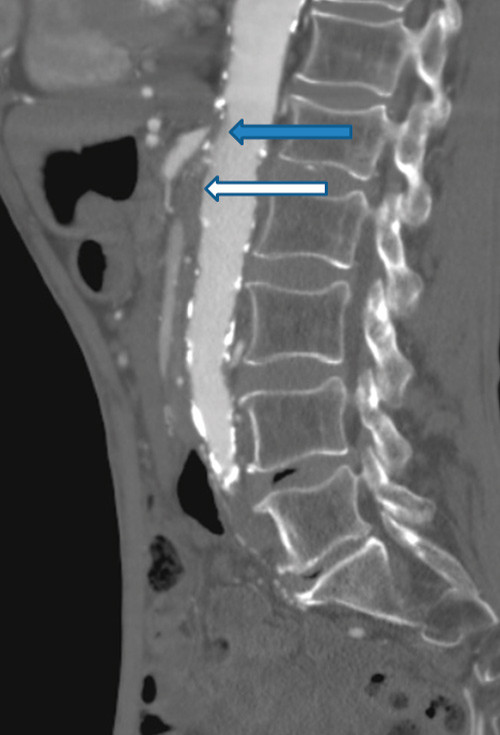

Man gransket på nytt CT abdomen utført for tre år siden. Undersøkelsen var gjort med intravenøs kontrast på mistanke om kronisk pankreatitt som årsak til magesmertene. Det ble ikke funnet tegn til pankreatittforandringer, men det ble bemerket uttalte arteriosklerotiske forandringer i abdominalaorta, proksimale bekkenkar, arteria mesenterica superior og truncus celiacus. De beskrevne forandringene i abdominalkarene ble den gang ikke fulgt videre opp. På bakgrunn av CT- funnet fra tre år tidligere valgte man nå å utføre abdominal CT- angiografi. Undersøkelsen viste en 2,5 cm lang okklusjon av a. mesenterica superior og en 8 mm lang okklusjon av truncus celiacus, begge okkludert fra avgangen fra lumbalaorta. A. mesenterica inferior var åpen, men med sannsynlig signifikant avgangsstenose, dvs. 75 % eller større reduksjon av karets tverrsnittsareal (fig 3).